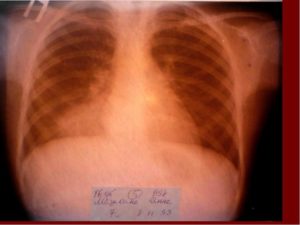

Клинически повторное заболевание, как правило, проявляется значительно сильнее, чем первичный случай. Однако на начальных этапах его трудно распознать, поскольку пациент может считать, что вновь появившиеся симптомы являются следствием ранее перенесенной болезни. Рентгенологическое обследование легких играет ключевую роль в определении характера протекания заболевания.

- Рентгенологическое исследование демонстрирует увеличение пораженной области или изменение характера заболевания на очаговое, что подразумевает наличие множественных поражений.

Установить более точный диагноз с определением степени поражения легкого (также, как распознать бронхит у ребенка и любое другое бронхолегочное заболевание) можно с помощью рентгенографии.

В медицинских источниках можно встретить различные определения повторной пневмонии. В педиатрической практике это заболевание характеризуется как два или более случая в течение одного календарного года, либо более трех эпизодов за неограниченный период времени. При этом рецидив подтверждается рентгенографическими данными, которые показывают освобождение легочной ткани при наличии инфильтрации.